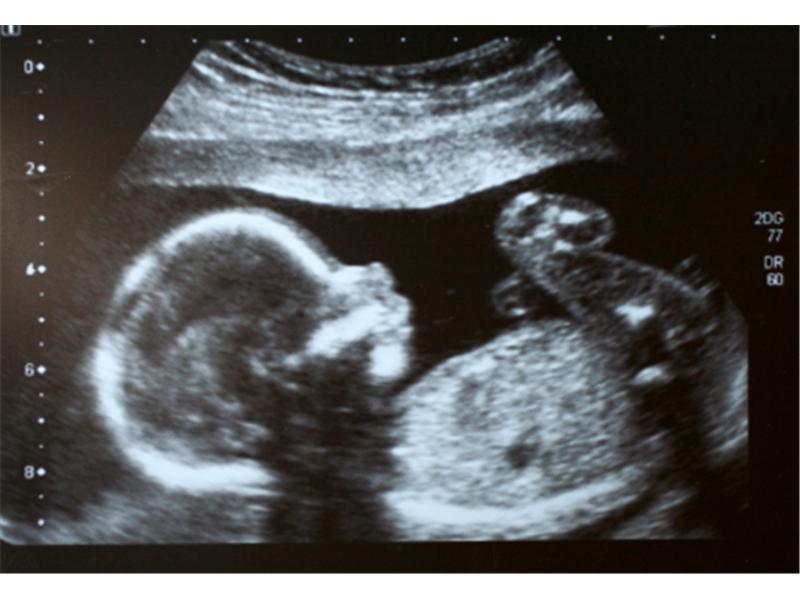

Úplně. Přijdete jako do kantýny, k okénku, embryolog se vás zeptá na jméno, řekne vám, kolik je embryí. To, že budou dvě, jsme se domluvili už předtím. Lehnete si na lehátko, koukáte na obrazovku a po zavedení vám dají fotografii dvou teček, s tím, že je to první snímek vašeho dítěte. Lehnete si na vedlejší lehátko a po půl hodině jdete domů.

Když jste uviděla ty dvě tečky…

Ano, byla jsem šťastná. Věřila jsem, že se to povede. Řekla jsem si: Jé, tak teď už tam jsou, a jak se mají, jaké to je asi pro ně? Ale že bych se cítila hned „těhotně,“ to vůbec. Jen jsem si říkala: tak teď už je tam něco navíc, teď si musím dávat větší pozor.